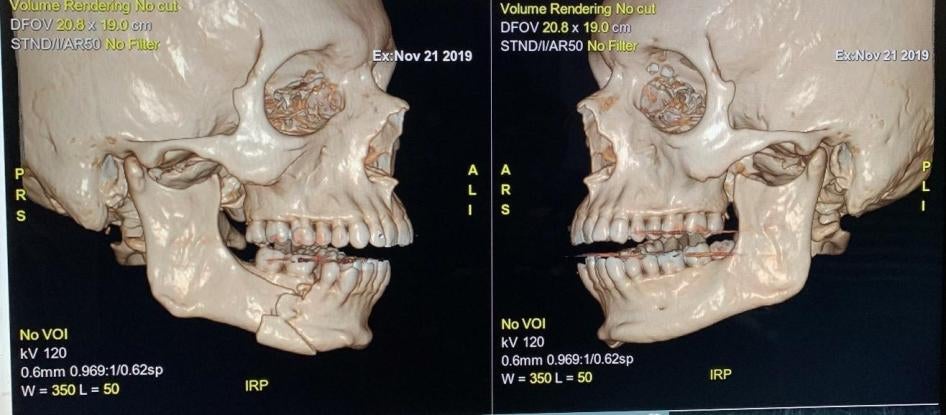

The most serious injuries include ocular lesions. At Del Salvador Hospital, where the vast majority have been treated, 77 percent of eye injuries were caused by pellets as of November 19, the Health Ministry told Human Rights Watch. Teargas cartridges caused the second most injuries.

- Ronald Barrales, 36, was participating in a demonstration in downtown Santiago on November 11 when people in front of a police truck started throwing rocks at it, he said. He was trying to walk past, when a police officer opened the passenger door, pointed a shotgun at him from eight meters away, fired, and hit him in the belly, chest, and left eye with pellets. Doctors told him he will never recover sight in that eye.

A 2012 internal report by the Chilean police made public on November 21 by local media outlets concluded that people hit by pellets from these shotguns at a distance of 25 meters or less could suffer serious injuries and even death. Even at 30 meters the pellets could cause injuries that would result in eye loss, the report warned.

The University of Chile’s Mechanical Engineering Faculty published a report on November 18 that found that pellets were 80 percent silica, barium sulphite, and lead, and only 20 percent rubber. On a scale of rigidity, they are as hard as a shopping cart’s wheel. Another study by medical experts at the Carlos Van Buren hospital reached similar conclusions after analyzing pellets they removed from patients.

- Juan Gabriel García Barco, 25, passed through a demonstration in downtown Santiago on November 11 as he was walking home. He passed a bridge where demonstrators were throwing stones at police vehicles blocking the way, when he was hit in the face with a projectile. He felt pain and had blood running down his face. He believes that it was a teargas cartridge, as he saw a police officer stick what he thinks was teargas riot gun out of one of the vehicles and heard a loud noise directly before he was hit. He also smelled teargas after being hit, he said. A witness said he saw police aiming at García Barco from a distance of roughly 5 meters. García Barco had no sight in his left eye when Human Rights Watch interviewed him three days later.

- Claudio Inda, 26, was standing in front of a bus close to Congress in Valparaíso during a demonstration on November 21, Inda’s partner told Human Rights Watch. When the bus drove away, he saw police on the other side of the street. The police shot a teargas cartridge directly towards where Inda was standing. Human Rights Watch reviewed a video filmed by a bystander showing the incident, which Inda said was filmed at the time. Doctors treating Inda at the Van Buren Hospital told Human Rights Watch that the cartridge broke his jaw.

- On October 28, a doctor at the Public Emergency Care Hospital (also known as Posta Central) in Santiago operated on a patient who arrived with one of these rounds inside his skull. The doctor said the round had fractured the patient’s skull, and such an injury posed a “serious risk” to the patient’s life. Possible consequences of this trauma must continue to be assessed for a year, he said.